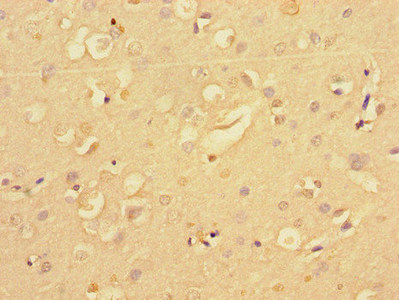

Immunohistochemistry of paraffin-embedded human brain tissue using CSB-PA015741LA01HU at dilution of 1:100